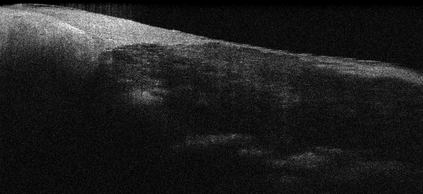

Coronary artery disease (CAD) is a cardiovascular condition with high morbidity and mortality. Intravascular optical coherence tomography (IVOCT) has been considered as an optimal imagining system for the diagnosis and treatment of CAD. Constrained by Nyquist theorem, dense sampling in IVOCT attains high resolving power to delineate cellular structures/ features. There is a trade-off between high spatial resolution and fast scanning rate for coronary imaging. In this paper, we propose a viable spectral-spatial acquisition method that down-scales the sampling process in both spectral and spatial domain while maintaining high quality in image reconstruction. The down-scaling schedule boosts data acquisition speed without any hardware modifications. Additionally, we propose a unified multi-scale reconstruction framework, namely Multiscale- Spectral-Spatial-Magnification Network (MSSMN), to resolve highly down-scaled (compressed) OCT images with flexible magnification factors. We incorporate the proposed methods into Spectral Domain OCT (SD-OCT) imaging of human coronary samples with clinical features such as stent and calcified lesions. Our experimental results demonstrate that spectral-spatial downscaled data can be better reconstructed than data that is downscaled solely in either spectral or spatial domain. Moreover, we observe better reconstruction performance using MSSMN than using existing reconstruction methods. Our acquisition method and multi-scale reconstruction framework, in combination, may allow faster SD-OCT inspection with high resolution during coronary intervention.